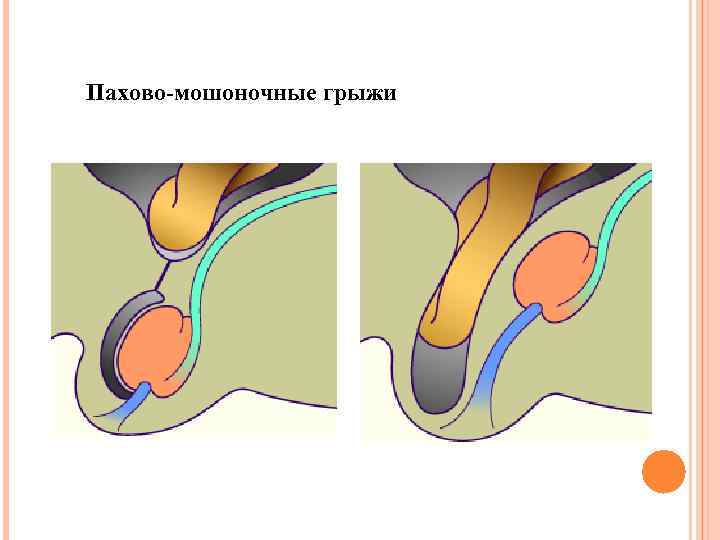

Пахово-мошоночные грыжи

Пахово-мошоночные грыжи